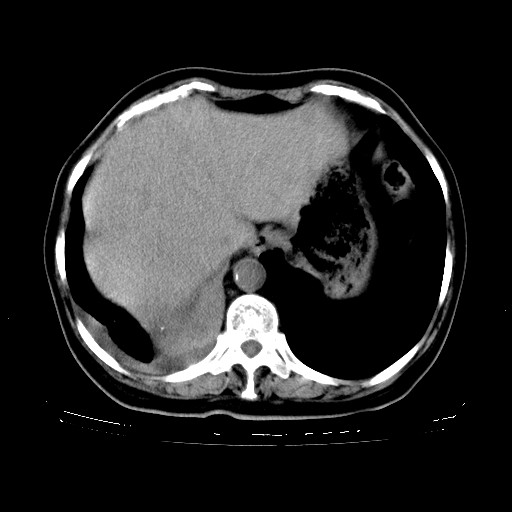

标题: CT23067:女,70岁,咳嗽、咳痰一个月,低热一周。 [打印本页]

女,70岁,咳嗽、咳痰一个月,低热一周。

1、右肺占位,考虑周围型ca 。

2、右下肺软组织密度肿块影,考虑肺隔离征。

3、两肺肺结核(右肺下叶背段及左肺)。

4、主动脉夹层。

5、右侧少量胸腔积液。